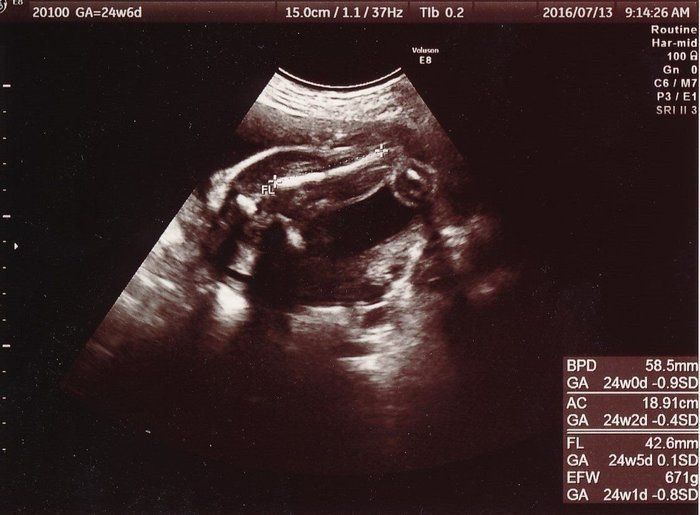

小吉さんの妊娠24週目のエコー写真

大腿骨の長さ(FL)から赤ちゃんの大きさを推定していたようです。推定体重は671gで、順調に大きくなってくれていることが分かります。先天性異常の検査をするかどうか自分なりに色々と考えましたが、1人目のときと同じくやはり見送ることに決めました。

こちらは4D写真で、赤ちゃんの右向きの横顔です。おでこから鼻、口元までが写っています。この頃からどうやら女の子っぽいということを度々聞くようになり、私が以前2回目に経験していた妊娠は「きっと女の子だった」という思いから、私の中では「うんうん」と頷いていました。